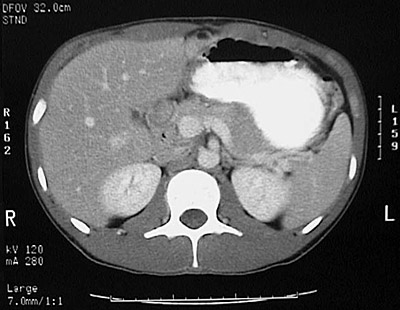

[L1] This is a normal abdominal CT scan with contrast demonstrating the liver and spleen and stomach filled with contrast and pancreas and upper pole of right kidney and upper pole of left kidney and aorta and right adrenal and left adrenal and inferior vena cava and splenic vein and crus of diaphragm and vertebral body and vertebral transverse process and vertebral spinous process and spinal canal in the upper abdomen.